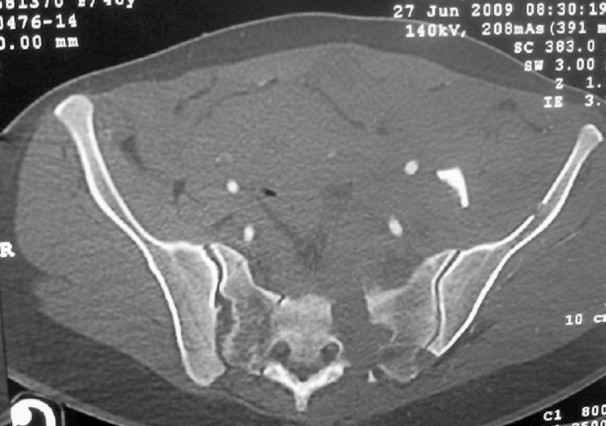

This patient has extensive and complicated skeletal injuries...much more data (such as additional relevant images and clinical information regarding the soft tissues and overall patient status) would help us formulate an informed plan.

The sacral pattern alone is quite difficult and seems to be some version of an H-pattern, but I can’t tell from these films.

The soft tissues are also in mild condition, buttock hematoma and probably a Morel-Lavalle. I send some more CT images. There are some conminution in the posterior column (I don’t have images now). The patient is scheduled for surgery next Monday. The plan is percutaneous sacral fixation and then ilioinguinal approach .

I am a huge fan of closed reduction and percutaneous posterior pelvic fixation, but that particular sacral injury warrants an open reduction.

I’d begin with that in order to have a high quality osseus foundation for subsequent acetabular repair.